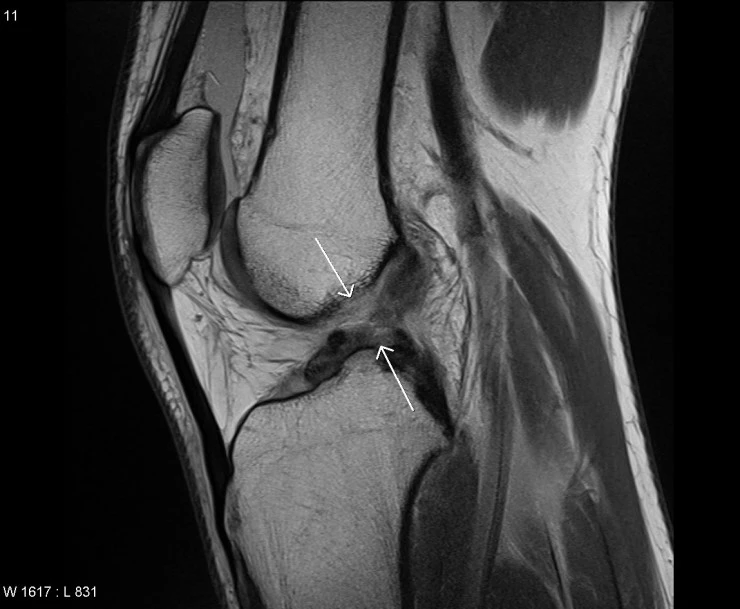

둘째, 초기 부종이 심해서 자세한 검사보다는 주로 MRI 촬영을 통해서 확인하게 된다.

급성적으로 손상을 받게 되면 일단 무릎은 엄청난 부종과 불안정함을 느끼게 됩니다. 그리고 관절의 움직임의 각도가 부족하게되며 관절선으로 압통과 보행의 어려움을 호소하게 됩니다. ACL의 손상의 경우 주로 MRI검사를 통해서 ACL의 연결을 확인하게 되며 다른 무릎 주변의 이상 역시 같이 체크하게 됩니다.

주로 이학적 검사는 Lachman's test를 통해서 관절의 불안정 정도를 검사하게 됩니다. 하지만 사실 부종이 심한 경우에는 이런 이학적 검사를 진행하기가 쉽지 않고, 다른 부분의 이상을 동시에 호소하는 경우가 많으며, 오히려 이 과정을 통해서 완전히 끊어지지 않은 ACL이 더 손상되는 경우가 있어서 주의해야합니다. 만약 완전히 ACL이 끊어지게 된다면 경골이 전방으로 완전히 당겨지는 느낌을 받게 됩니다.